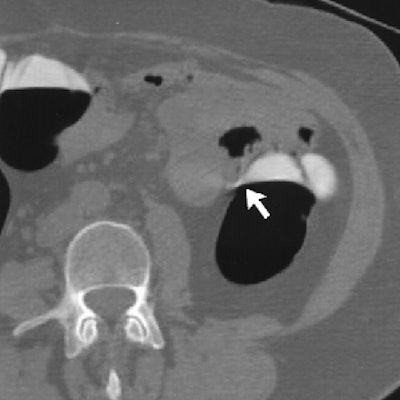

Polypoid artifacts related to partial-volume effects are a more serious shortcoming of the primary 3-D read, according to the group. Such artifacts tend to occur where air-fluid levels interface with the colon wall, especially when a meniscus effect is also present, the group wrote. Air-fluid haustral-fold interfaces are another characteristic location of polypoid artifacts, making evaluation of the uncleansed 2-D images vital for accurate interpretation. Since these artifacts result from the cleansing process, they are often present on the electronically cleansed 2-D images as well.

| Above, uncleansed 2-D image of the same average-risk 54-year-old man undergoing VC screening obtained with patient in supine position shows air-fluid-wall interface (arrow) corresponding to level of "polyp" on cleansed 2-D images (not shown). Note the utility of uncleansed images in avoiding a false-positive finding. (Image and caption used with permission of the American Roentgen Ray Society from AJR, © September 2003, Vol. 181:3, pp. 799-805.) |